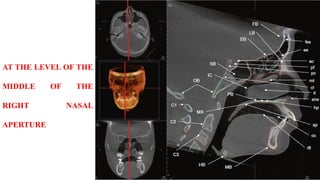

AT THE LEVEL OF THE

MIDDLE OF THE

RIGHT NASAL

APERTURE

AT THE LEVELOF THE MIDDLE OF THE RIGHT NASAL APERTURE